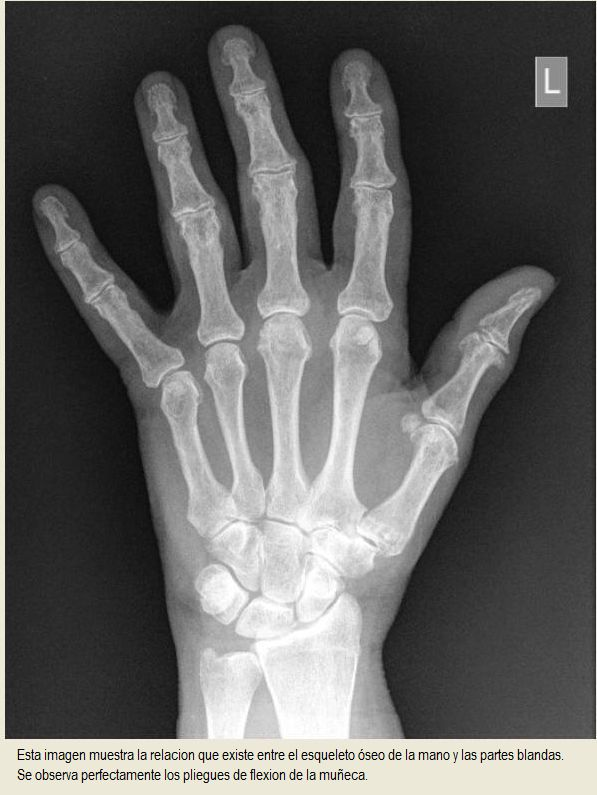

De abajo hacia arriba , en la imagen radiológica , tenemos : El cúbito y el radio , encima el carpo con sus huesecillos,los cinco metacarpianos y las falanges de los dedos de la mano .

Como observamos en estas imágenes en las que se aprecia tanto el esqueleto como las partes blandas, la palma de la mano comprende huesos del carpo, los cinco metacarpianos y parte de las falanges de los dedos a excepción del pulgar.

Al igual que observamos que la muñeca comprende los huesos del carpo, su articulación con los metacarpianos de un extremo y su articulación con el radio del otro extremo. |